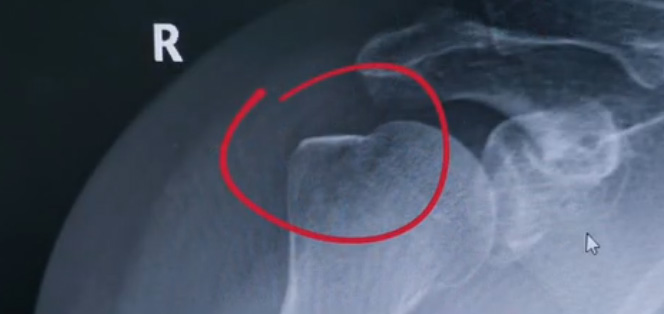

肩關(guān)節(jié)的X射線片子,看到?jīng)]有明顯的骨折,但是實(shí)際上已經(jīng)骨折了。那么是如何發(fā)現(xiàn)的呢?醫(yī)生對于做出疾病診斷的時(shí)候,會(huì)選擇什么樣的檢查方式。也更好的配合醫(yī)生,來解決問題。1米高的地方摔了下來,右側(cè)肩關(guān)節(jié)與地面相撞受傷了。當(dāng)時(shí)的胳膊還能活動(dòng),疼痛感很明顯,但是在家觀察了一天,這個(gè)腫脹沒有明顯的加重。然而問題是什么呢?疼痛始終不能緩解,所以就需要到醫(yī)院檢查。醫(yī)生查看關(guān)節(jié)的受限也很明顯,尤其做外展這個(gè)動(dòng)作的時(shí)候,幾乎沒辦法自行完成。肩關(guān)節(jié)內(nèi)的這個(gè)韌帶和肌腱可能還沒有發(fā)生嚴(yán)重的損傷。

首先做一個(gè)普通的X光檢查,看一看有沒有大的骨折或大的問題。結(jié)果是沒有發(fā)現(xiàn)太嚴(yán)重骨折損傷問題。結(jié)合病史,還是有點(diǎn)疑惑。因?yàn)樘鄣奶珔柡?。x光檢查和他的疼痛之間不匹配,患者沒有骨頭的損傷,疼痛不至于達(dá)到這么嚴(yán)重的一個(gè)程度。是否有一種情況掩蓋住了病情。這也是X線檢查的通病。x光檢查它是一個(gè)二維的檢查,有可能患者肩關(guān)節(jié)啊發(fā)生了骨折。但是它的位置被前方或者側(cè)方的這個(gè)骨頭遮擋住了。不是立體的就沒辦法看到后方的情況。想要更加進(jìn)一步的明確問題,判斷是否有骨頭的損害怎么辦?

進(jìn)一步就是查CT,可以更全面的角度去判斷問題的所在。就會(huì)發(fā)現(xiàn)是否骨折可以看到確實(shí)存在著骨折,還好骨折不算嚴(yán)重。可以說是一個(gè)骨裂。這個(gè)肩關(guān)節(jié)與地面撞擊的時(shí)候,暴力沒有達(dá)到那么強(qiáng)。讓骨頭整個(gè)發(fā)生一個(gè)巨大的斷裂,而是造成了一個(gè)小的劈裂。適當(dāng)?shù)倪M(jìn)行一些抗炎止痛藥的使用。適當(dāng)?shù)倪M(jìn)行一些消腫治療,患者癥狀也就消失了。